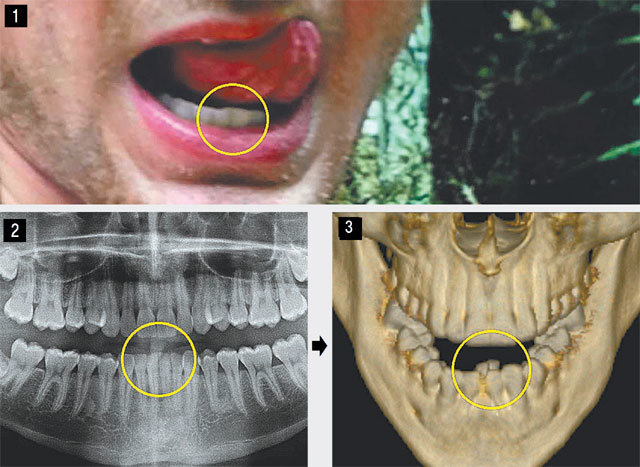

北朝鮮から昏睡状態で解放され、死亡した米国人大学生のオットー・ワームビアさんが「ボツリヌス菌による食中毒になり、治療中に睡眠薬を服用して昏睡状態に陥った」という北朝鮮当局の説明は事実とは異なると専門家が見ていることが分かった。「ボイス・オブ・アメリカ」(VOA)によると、ワームビアさんを診察した歯科医は、米連邦裁判所に提出した意見書で、「ワームビアさんの下の2本の歯の位置が物理的衝撃によって変形していた」とし、暴力や拷問の可能性を提起した。別の医師は「死因は脳損傷と推定される」と明らかにした。